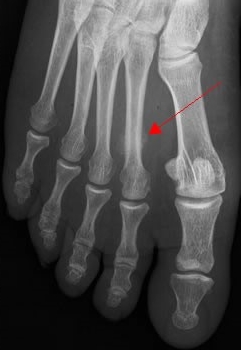

La radiographie :Attention, au début, la radiographie est presque toujours normale. Les fissures sont trop fines pour être vues. Elle ne devient positive que plusieurs semaines plus tard, en montrant des signes de consolidation (cal osseux).

Radiographie d’une fracture du IIe métatarsien du pied.